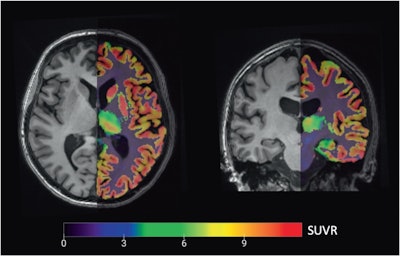

PET/MRI images used in the analysis: Axial (left, through the prefrontal volume-of-interest) and coronal (right, through the hippocampal volume-of-interest) overlay of a partial volume corrected carbon-11 UCB-J PET image (right subparts) registered to the anatomical T1-weighted MRI background for delineation.Image courtesy of Translational Psychiatry

The group enrolled 24 currently depressed adults with late-life depression (average age, 73 years old) and 36 age- and gender-matched healthy controls (average age, 70 years old). Participants underwent simultaneous C-11 UCB-J PET and 3D T1- and T2-weighted fluid-attenuated inversion recovery (FLAIR) MRI on a 3-tesla PET/MRI scanner.

Thus, in this study, the researchers performed a prospective analysis to measure synaptic density and gray-matter volume in a group of patients. For the PET imaging, they used a radiotracer named carbon-11 (C-11) UCB-J, which binds to a glycoprotein expressed in virtually all synapses.